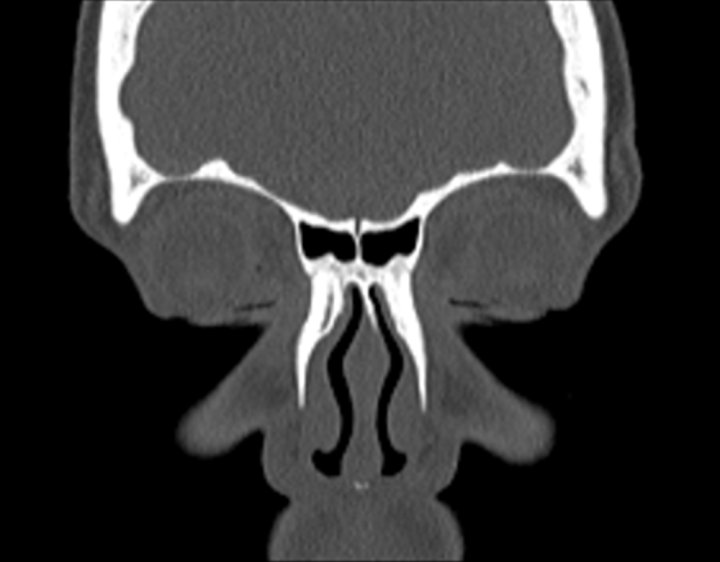

Click any image for labels.